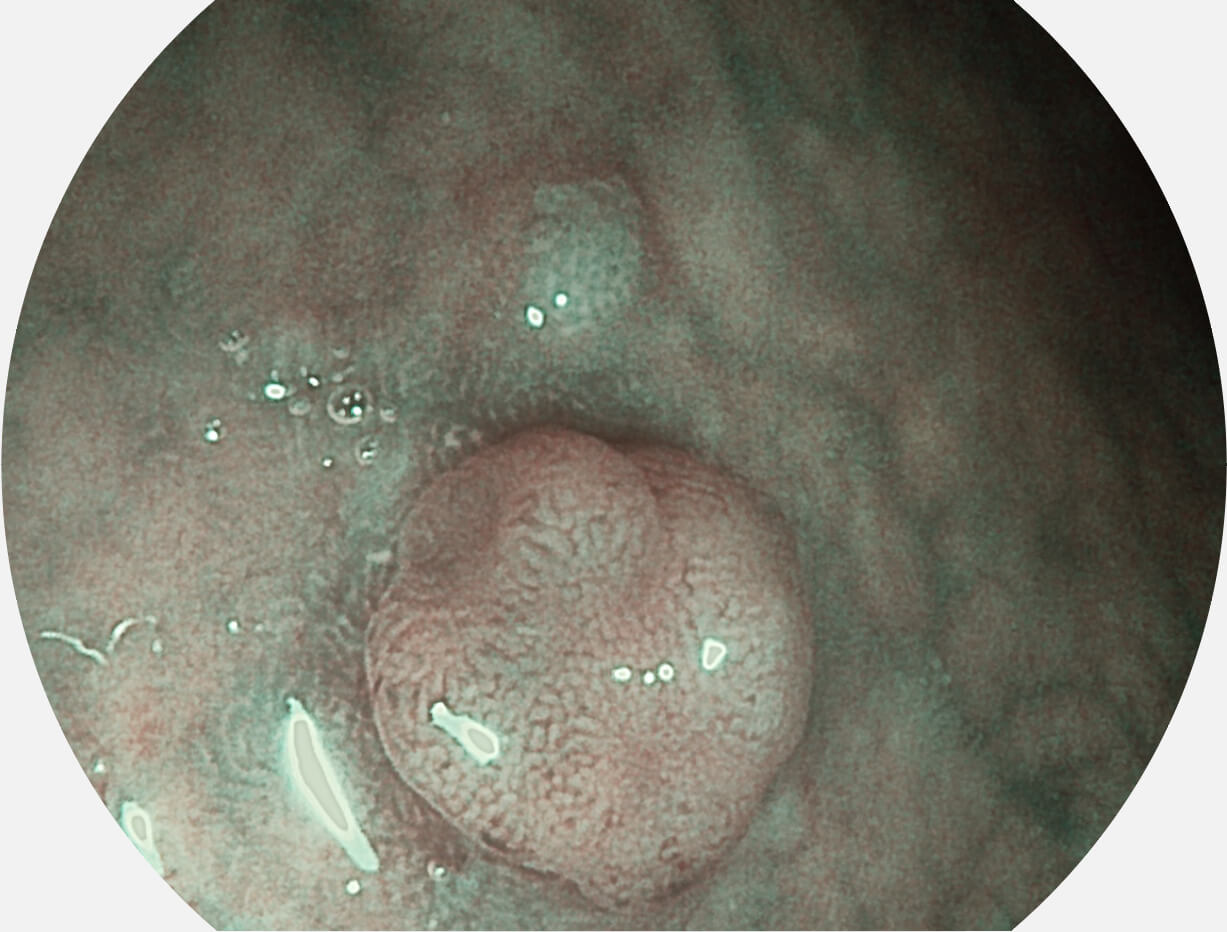

图像具有高亮度、高黏膜血管颜色对比度的特点,且不改变粘液、食物残渣、粪便的基本颜色,可在中远景下进行观察,助力消化道早期疾病的诊断。

SFI图像